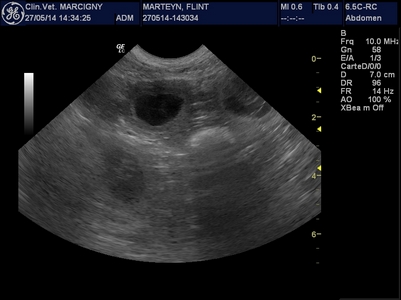

Le mariage de Genkini et Flint'on va porter ses fruits ! De belles petites "bulles de bonheur" nous ont fait coucou lors de l'échographie :-)